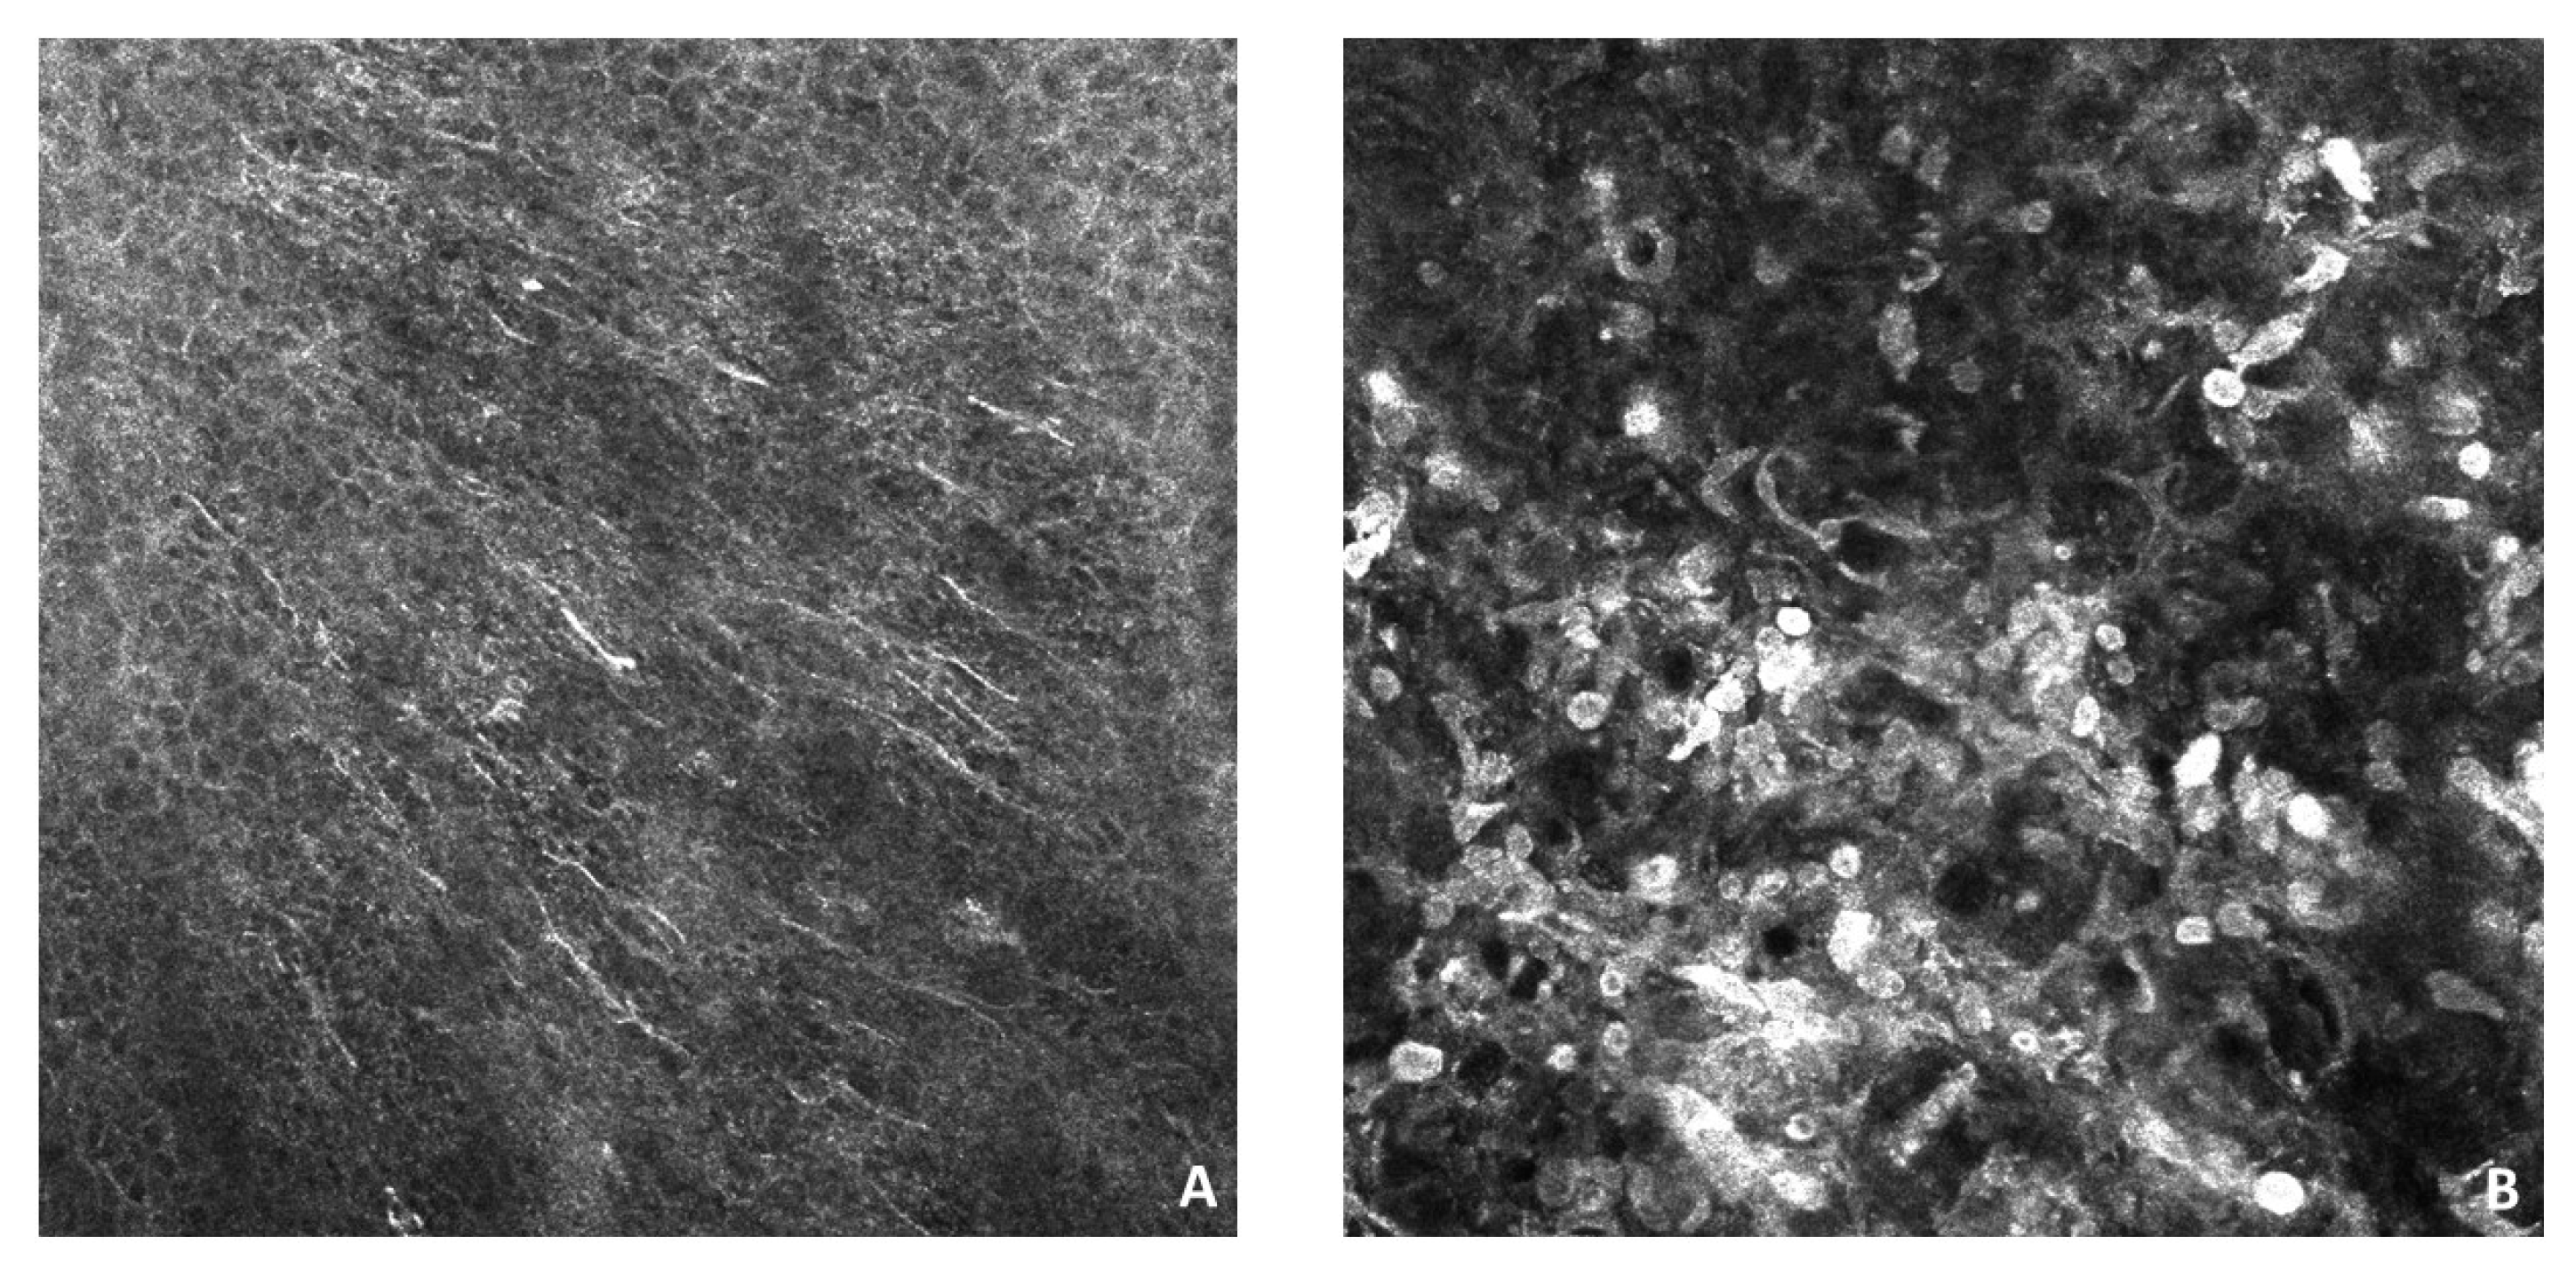

| Author | Age at the Diagnosis (y) | Dermoscopy | Histology |

|---|---|---|---|

| Mendes et al. [16] | 11 | Globular pattern: multiple pigment globules of different size | Compound melanocytic nevi |

| Alves de Souza et al. [17] | 9 | Compound pattern: fine pigmented network (periphery) and darkened globules of multiple size (center) | Compound melanocytic nevi |

| Savas et al. [19] | 3 | Globular pattern: scattered pigmented globules of varying size on a pigmented area with a pigmented center and dark periphery | Compound melanocytic nevi |

| Correia et al. [21] | 14 | Compound pattern: pigmented patch with dark dots and discrete annular-granular structures (prepuce) and a darker pigmented patch with greater density dark dots (glans) | Compound melanocytic nevi |

| Our case | 57 | Compound pattern: fine pigmented network (periphery) and darkened globules of multiple size (center) | Compound melanocytic nevi |